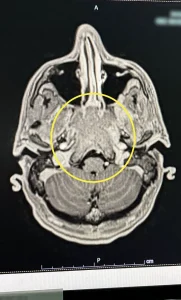

An MRI scan and biopsy revealed a malignant tumor in his sinuses called Nasopharyngeal Small Cell Neuroendocrine Carcinoma (NPC).

Emergency hospital admission followed, leading to an MRI that uncovered the rare and aggressive tumor.